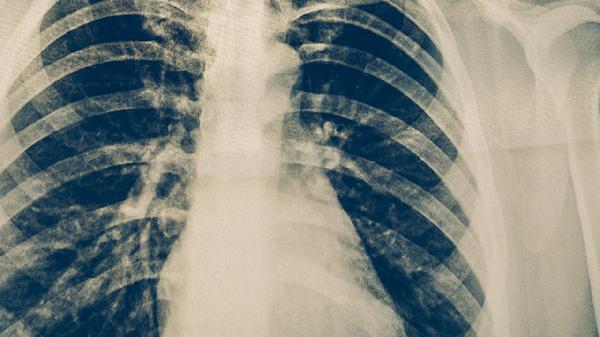

慢性肺心病最常见的病因是什么

慢性肺心病最常见的病因是慢性阻塞性肺疾病,其次为支气管哮喘、肺结核、支气管扩张等慢性肺部疾病。慢性肺心病主要由长期肺部疾病导致肺动脉高压,进而引发右心室结构和功能改变。